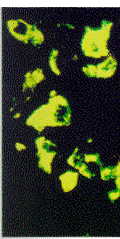

2.1 特定共存 脑垂体前叶的内分泌细胞用两种促肾上腺皮质激素和嗜铬颗粒素C[2]抗体进行染色. 分别用568 nm和488 nm激发(氩/ 氪激光),用间断采集方式(sequentially)分别采集红色和绿色图象(图1a). 图1b和1c示LaserSharp共存分析对话框和从复合图象中生成的红色和绿色荧光强度的荧光分析图. 背底和渗透(bleed-through)从数据中(注意:不是从图象中)被选择并去除,同时显示两个共存系数(见后). 红色共存系数是Red=0.83,绿色共存系数是Green=1.0. 这意味着有某些红色象素中没有绿色成分,但它们大部分是共存的. 所有绿色象素都与剩余的红色象素共存. 图2a显示的是如何选择部分荧光分析图来分割图象数据,图2b显示所选择的象素用白色在图象上突出显示.

图1a 免疫荧光标记垂体前叶内分泌细胞中促肾上腺皮质激素与嗜铬颗粒素,用间段采集方式分别采集红色(TR标记)绿色(FITC标记)以及复合图象.